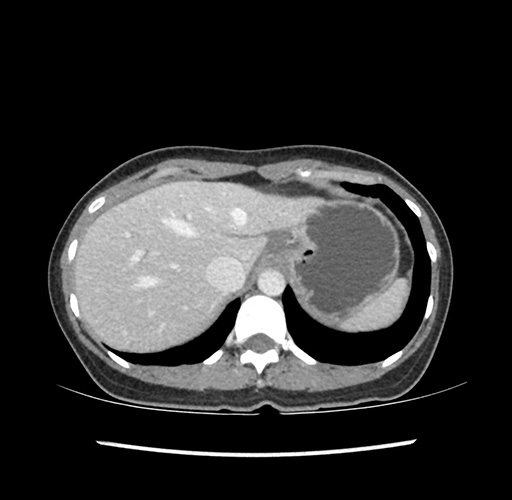

Imaging Analysis

Look through the patient's CT scan to identify any areas of concern for the necessary procedure.

Based on your CT findings, which issue(s) would give reason for "planned slowing down moment(s)" in this case?